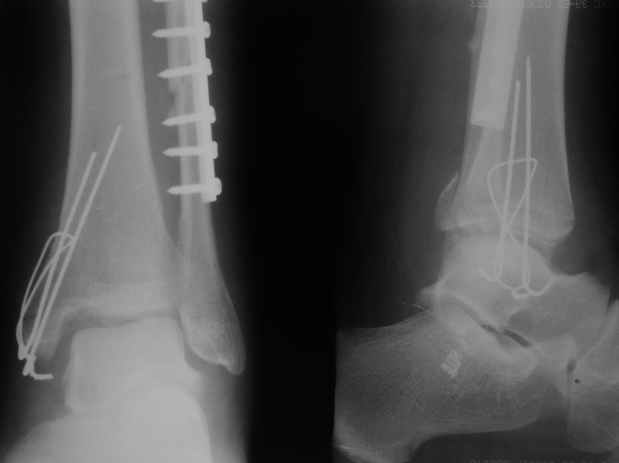

Здесь похожий случай трехнедельной давности, перелом почти сросся и была укорочена малоберцовая, на операции длину малоберцовой смогли восстановить только после того, когда проксимальнее пластины ввели шуруп и использовали его как толкатель, с помощбю дистракционого инструмента (lamina spreader).

Меньше всего волнует положение медиальной лодыжки - в любое время можно провести остео или реостеосинтез, при несращении можно просто резецировать без ущерба для движений в голеностопе. Здесь обошлись фиксацией одним 4 мм канюлированным шурупом.